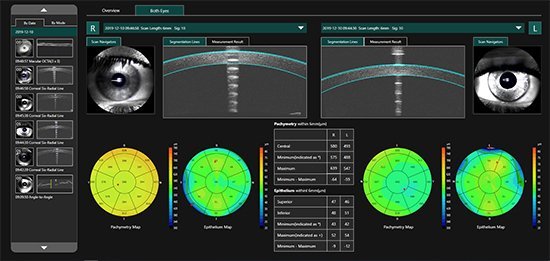

MOCEAN 4000

SLO-OCT e OCTA com VASCAN ADVANCE

O Mocean 4000 é configurado com os sistemas de imagens combinados SLO-OCT de ponta e o rastreador ocular baseado em SLO, uma plataforma poderosa para aplicações avançadas, como a angiografia OCT.